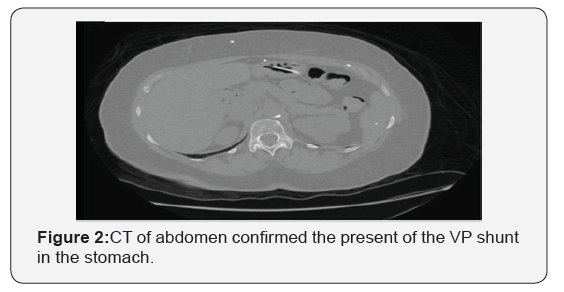

A 65-year-old African American woman was referred because of iron deficiency anemia. She had no gastrointestinal symptoms and fecal immunochemical test was negative 3 months ago. Colonoscopy was unremarkable. EGD showed no evidence of peptic ulcer disease or any arteriovenous malformation up until the 4th part of duodenum. Incidentally, it was noted that she had a foreign body protruding into the gastric fundus (Figure 1). On review of her past medical history, she had a VP shunt procedure in 1995 after clipping of an intracranial aneurysm. She also had a shunt revision in 2015. CT of abdomen confirmed the present of the VP shunt in the stomach (Figure 2). The tip of the tube appeared to be buried within the greater curvature of the stomach.